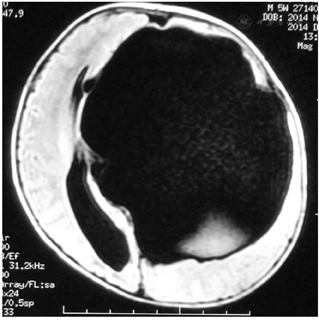

入院后行蛛网膜囊肿-腹腔(Cystoperitoneal,CP)分流术,初始开放压力设定为18 cmH2O,后每间隔3-6月调低2-3 cmH2O;术后2月MRI发现蛛网膜囊肿缩小;术后22月MRI发现囊肿进一步缩小,可见囊肿内分隔和透明隔,进一步行内镜下囊肿分隔和透明隔造瘘术,术后每2-3月逐步将分流阀压力从9 cmH2O调至15cmH2O;造瘘术后3月复查MRI发现囊肿进一步缩小、脑皮层增厚;

MRI检查示左侧额颞顶部巨大蛛网膜囊肿,脑组织严重受压,伴有脑积水,2014-12行蛛网膜囊肿腹腔分流术,初始开放压力设定为18 cmH2O,后每间隔3-6月调低2-3 cmH2O;术后2月MRI发现蛛网膜囊肿缩小;术后22月MRI发现囊肿进一步缩小,可见囊肿内分隔,入院进一步行内镜下囊肿分隔和透明隔造瘘术,术后逐步将分流阀压力9cmH2O调至15cmH2O;